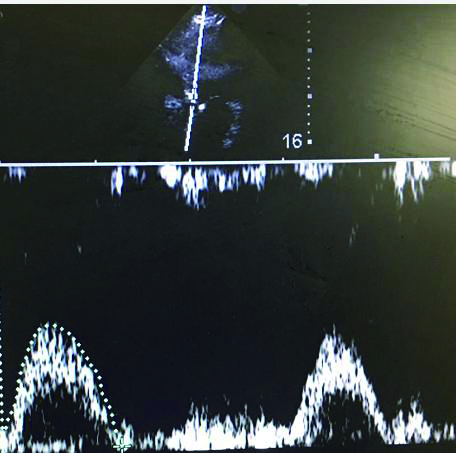

(1)半卧位抬高45°维持2 min,用超声测得CO指标,作为基线数值;(2)取仰卧位,下肢抬高45°维持1 min,用超声记录CO指标;(3)取步骤一体位,维持2 min,测量超声CO数值,评估CO指标是否回至基线数值[8]。见图 2。

| 图 2 PLR试验操作步骤 Figure 2 The procedure of passive leg raising test |

充分暴露前胸部,于胸骨旁长轴切面,选取主动脉瓣根部测量左室流出道直径与截面积。选取心尖五腔心切面,通过脉冲多普勒测量动脉流速,计算左心室流出道收缩高峰期的流速时间指数,测量心率,最后通过心脏检查软件包自动计算出CO(图 3、4)。通过上述PLR试验,联合超声获得的CO,最后计算ΔCO值,ΔCO≥15%定义为容量反应性阳性;反之为容量反应性阴性。